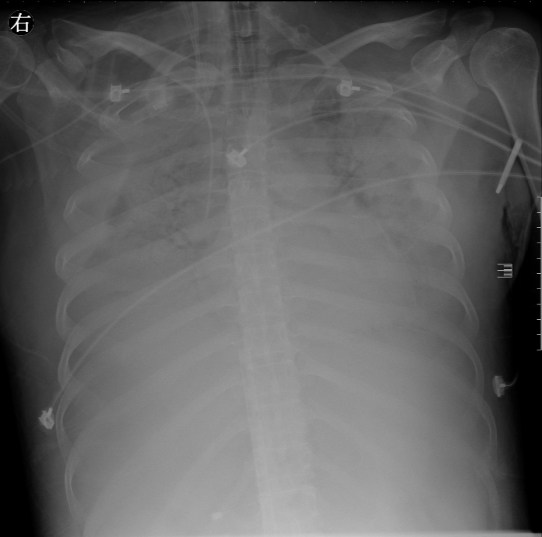

本以为曙光就在眼前,可一转眼,病情就出现了变化。急转直下,又是生死考验。患者术后出现严重的急性呼吸窘迫综合征,肺部感染几乎呈现“白肺”状态,生命垂危。并且因凝血系统严重受损,腹腔内手术伤口不断渗血,ICU团队持续为患者补充血小板及各种凝血因子等对症治疗后,并无改善。

在持续进行4天、每天7~9小时的俯卧位通气治疗后,患者的影像学检查X片明显较前改善。期间,随着情况稳定转好,ECMO各项指标也都达到了撤机标准。11月25日,ECMO成功被撤除,实施床旁持续CRRT治疗,患者的生命体征趋于平稳。看到患者一步步转危为安,家属与医护团队都非常激动。